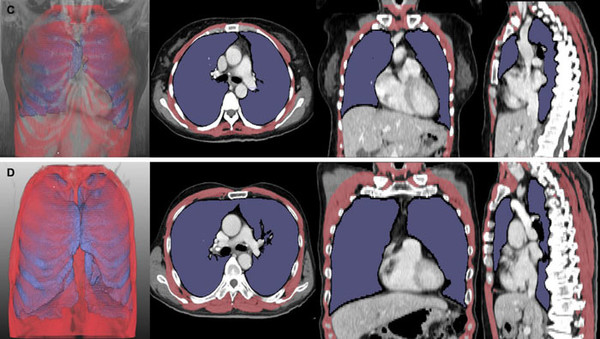

이에 연구팀은 딥러닝 소프트웨어를 이용해 루게릭병 환자의 폐와 호흡근 위축 정도를 나타내는 폐 용적 지수(LVI)와 호흡근 용적 지수(RMI)*를 개발하고, 병기 및 생존 기간과의 연관성을 확인했다.

그 결과, 폐·호흡근 용적 지수는 병기(1~4기)가 증가할수록 유의미하게 감소했다. 또한, 이 지수들이 낮은 그룹은 높은 그룹 대비 폐와 호흡근 위축이 뚜렷한 것으로 나타나, 기관절개술 또는 사망에 이르는 시점이 빨랐다.

이 결과는 구음장애 환자만 분석한 경우에도 동일하게 나타나, 연구팀이 개발한 영상 기반 지표가 호흡 기능을 평가하기 어려운 루게릭병 환자에서도 폐활량 검사를 대체할 수 있는 가능성을 보여줬다.